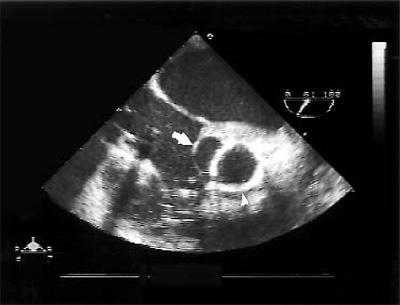

An intraoperative TEE (Fig. 1) confirmed the presence of a nonruptured ASV. A transverse aortotomy was made 5 mm above the sinotubular junction (STJ), in healthy tissue above the lesion. The STJ was sized at 25 mm, and the aortic annulus was estimated at 27 mm. A 27-mm Freestyle® aortic root bioprosthesis (Medtronic, Inc.) was selected. The ASV was measured, and its perimeter was smaller than the height and width of the porcine aortic wall adjacent to the noncoronary cusp. The bioprosthesis was then rotated 120 degrees in order to position its right sinus over the patient's affected noncoronary sinus. This maneuver enabled us to completely cover the ASV with the bioprosthesis. Interrupted 4-0 braided polyester inflow sutures were placed on a plane parallel to and below the aortic annulus. The valve was seated and trimmed (Fig. 2). The ASV was then completely excluded with the continuous outflow suture line. Before we declamped the aorta, warm cardioplegic solution was infused, followed by warm blood. Blood infusion was continued via the coronary sinus until strong cardiac contractions were present and air bubbles were no longer visible in the TEE. The remainder of the operation was completed in the usual manner. Intraoperative TEE, with volume and pressure loading, demonstrated complete exclusion of the ASV (Fig. 3).

Fig. 3 Intraoperative transesophageal echocardiogram shows complete exclusion of the aneurysm of the sinus of Valsalva (arrow) by the Freestyle bioprosthesis (arrowhead).